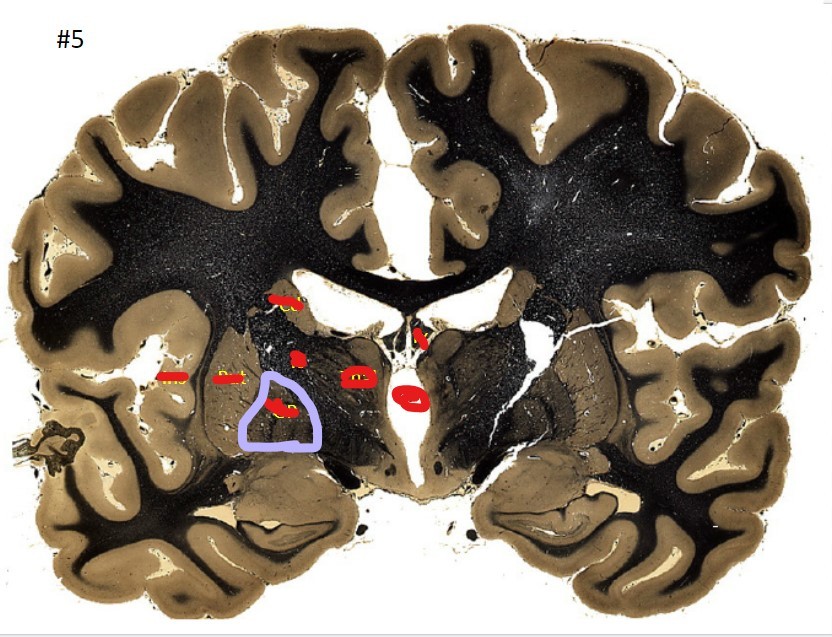

Q

what is the circled area (#5)?

A

the caudate nucleus

20

21

the 3rd ventricle

22

23

the globus pallidus

24

25

the internal capsule

26

the putamen

27

the amygdala

28

the beginning of the hippocampus